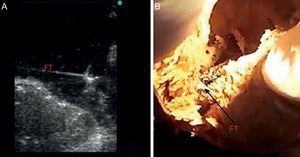

MÉTODOSInvestigación básicaEstudio anatómicoEn primer lugar, se diseñó un estudio para conocer la prevalencia real del FT en corazones humanos mediante la disección anatómica. Se seleccionaron 41 cuerpos de cadáveres humanos de edades entre los 65 y los 88 años —18 mujeres y 23 varones— procedentes de donaciones voluntarias, en el periodo de enero a noviembre de 2012. Los cuerpos se fijaron previamente mediante perfusión por cánula implantada en arteria carótida común y posterior conservación en balsas con solución de formol al 5%. Se extrajeron los corazones mediante toracotomía, se etiquetaron del 1 al 41, se pesaron con báscula de precisión y se midieron en longitud y anchura con pie de rey. También se midió el grosor del septo interventricular y la pared lateral. Con bisturí se realizaron incisiones de la pared lateral del ventrículo izquierdo, para permitir la visualización del interior del ventrículo izquierdo y los FT, que se definen anatómicamente como estructuras fibromusculares con origen en el septo interventricular que cruzan el ventrículo izquierdo hasta los músculos papilares o la pared lateral o el ápex cardiaco. Se estudiaron los FT en número, localización y grosor; 10 de los corazones disecados con FT visible se sumergieron en una cubeta con agua para realizar ecografía directa de dicha estructura (figura 1).